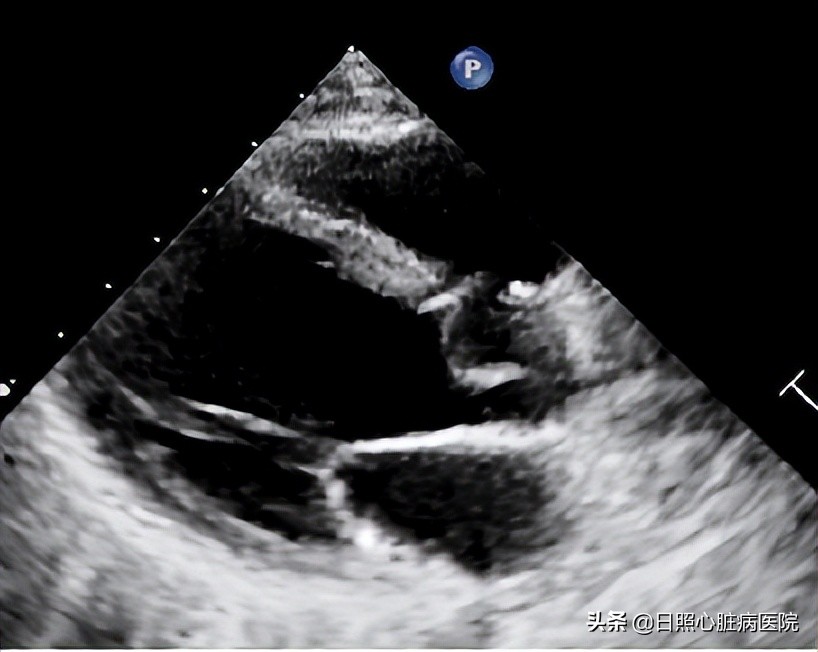

当出现室间隔缺损相关的临床表现时需要做心电图、胸部x线片检查、超声心动图检查帮助诊断。其中超声心动图是首选的检查手段,它可以精确的诊断出缺损口大小、分流及部位。

介入治疗是指在X线或者超声心动图的指引下,通过穿刺血管将封堵器送至室间隔缺损边缘,释放封堵器以达到缺损封堵的一种方法。